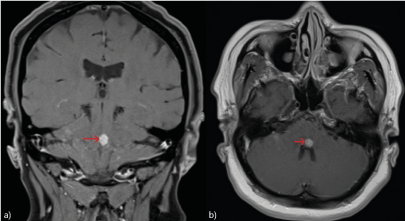

Magnetic resonance imaging (MRI) of the brain, at the time of diagnosis of NSCLC, showed multiple small enhancing lesions consistent with metastases in the left parietal lobe, right cerebellar hemisphere, right frontal lobe and in the brainstem at the pontomedullary junction, abutting the floor of the fourth ventricle (Figure 1). A subsequent MRI twelve months later (prior to the current presentation) showed interval development of radiation-induced leukoencephalopathy and bilateral hypertrophic olivary degeneration (HOD) demonstrated by an increased signal within the inferior olives on T2-weighted and fluid-attenuated inversion recovery (FLAIR) imaging as depicted in (Figure 2). Cerebrospinal fluid (CSF) did not show evidence of an inflammatory cause (WCC 1 x 106/L, protein 0.25 g/L) or leptomeningeal disease and an electroencephalogram (EEG) showed non-specific generalised slowing. Antineuronal antibodies were negative on serum and CSF.

Figure 1: MRI brain on diagnosis

T1-weighted MRI post-contrast a) coronal and b) axial sequence at the time of diagnosis of NSCLC showing a metastatic deposit in the posterior midbrain in the floor of the fourth ventricle (red arrows)